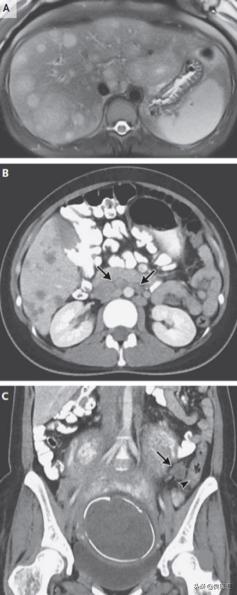

体温36.6°C,心率96次/分,血压105/68 mmHg,氧饱合度97%,右上腹压痛,妊娠子宫软,无肋骨痛。淀粉酶、脂酶和白细胞分类正常,多普勒超声可见胎心搏动,胎儿发育符合妊娠时间,生理指标正常。超声见肾脏和膀胱正常,肝脏弥漫异质性回声,有大量肿物。腹部MRI见肝脏多发病灶,T2加权像高信号,T1加权像低信号,最大损害7.4cm×3.9cm,部分中心坏死(图1A)。

给予别嘌醇和静脉补液,入院1天后转诊至第二家医院进一步评估。胸腹盆腔增强CT见大量低密度肝损害,部分边界清,最大损害8.2 cm,腹主动脉周围和门腔静脉周围淋巴结增大(图1B)。经皮肝活检提示转移性腺癌。患者未遵医嘱自行离院,经其产科医师转诊至麻省总院产科,此时孕33周。

图1 腹部影像学。A. 腹部MRI,T2加权像见多发高信号;B.盆腔CT见多发腹主动脉周围淋巴结(箭头);C. 盆腔CT见乙状结肠增厚(短箭头)伴邻近淋巴结肿大(箭头)。